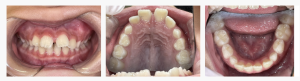

【叢生】早期矯正|7歳女児|治療期間24ヶ月

みなさんこんにちは。 兵庫県明石市魚住町、西江井ヶ島駅から徒歩6分、 こどもの矯正に強い明石市の歯医者、ハローこどもファミリー歯科です。 今回は、「ガタガタしているのが気になる」というご相談をきっかけにスタートした、 7歳女の子の叢生(そうせい)早期矯正症例をご紹介します。 &nb…